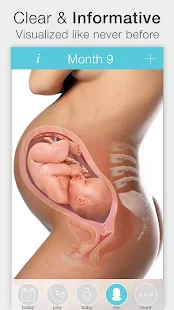

Pregnant? Get the worldwide No.1 Pregnancy App. Approved by the NHSWant to see beautiful, interactive images for every week of your pregnancy? Join more than 4 million users who already use this Pregnancy App to follow their pregnancy.

- Color and scan images

Pregnancy+ is recommended by healthcare providers and pediatricians. This Pregnancy App was created by Health & Parenting together with leading healthcare professionals.